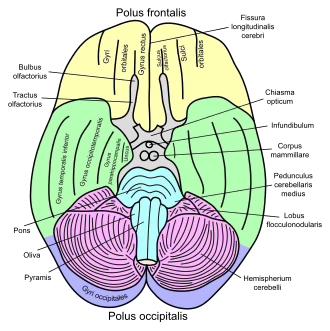

Human brain seen from below. Parahippocampal gyrus shown in blue | |

Basal view of a human brain.

Basal view of a human brain. -